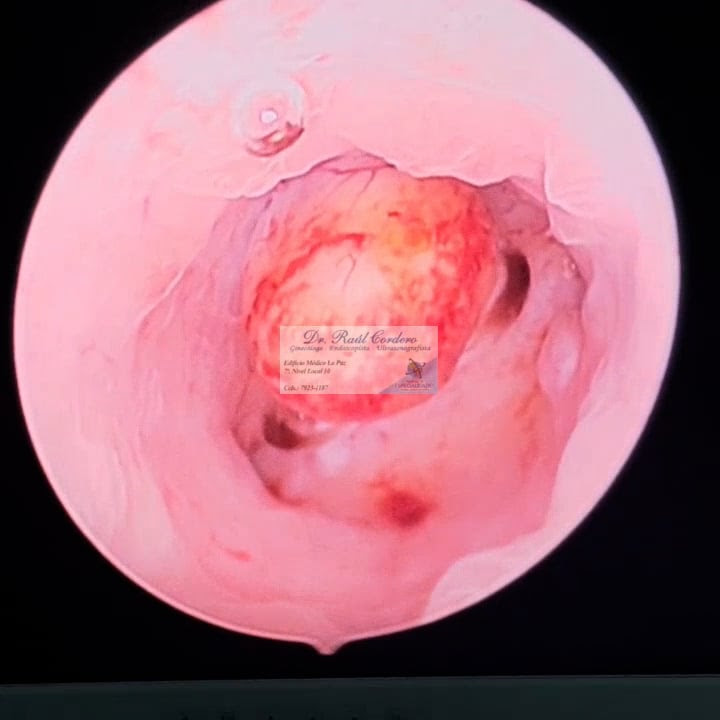

User Image Dr. Raúl Antonio Cordero Sorto

Fibroma uterino submucoso por vídeo histeroscopia

Ginecologos Y Obstetras > Ginecolologo Obstetras

VER VIDEO